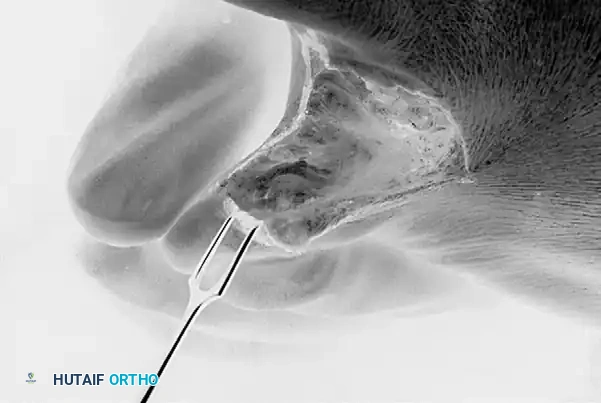

Exposure of the web space and meticulous resection of the lateral base of the fourth proximal phalanx using a sharp osteotome or sagittal saw.

Exposure and resection of the medial aspect of the proximal fifth toe. Note the careful protection of the surrounding soft tissue envelope.

Following the initial resection, the surgeon must manually compress the fourth and fifth toes together to simulate a weight-bearing, shod foot. The web space is deeply palpated to determine if any residual bony impingement exists. If the resection seems inadequate or if impingement persists, the opposite bony offender must also be resected.